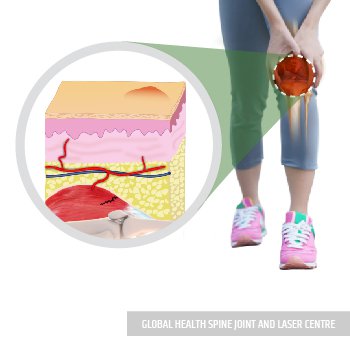

Damage or disease that affects any of these(the lower part of the thighbone, the upper part of the shinbone, and the kneecap.) structures may lead to pain.

Laser Beam is applied to the knee for treating all damage.

Laser Beam increased oxygenated blood to the injured tissue accelerates tissue healing.

Repair of damaged muscle fibers & activation of myogenic satellite cells leads to regeneration of muscle tissue.

After Laser Treatment, cartilage deposition and joint functions are improved.